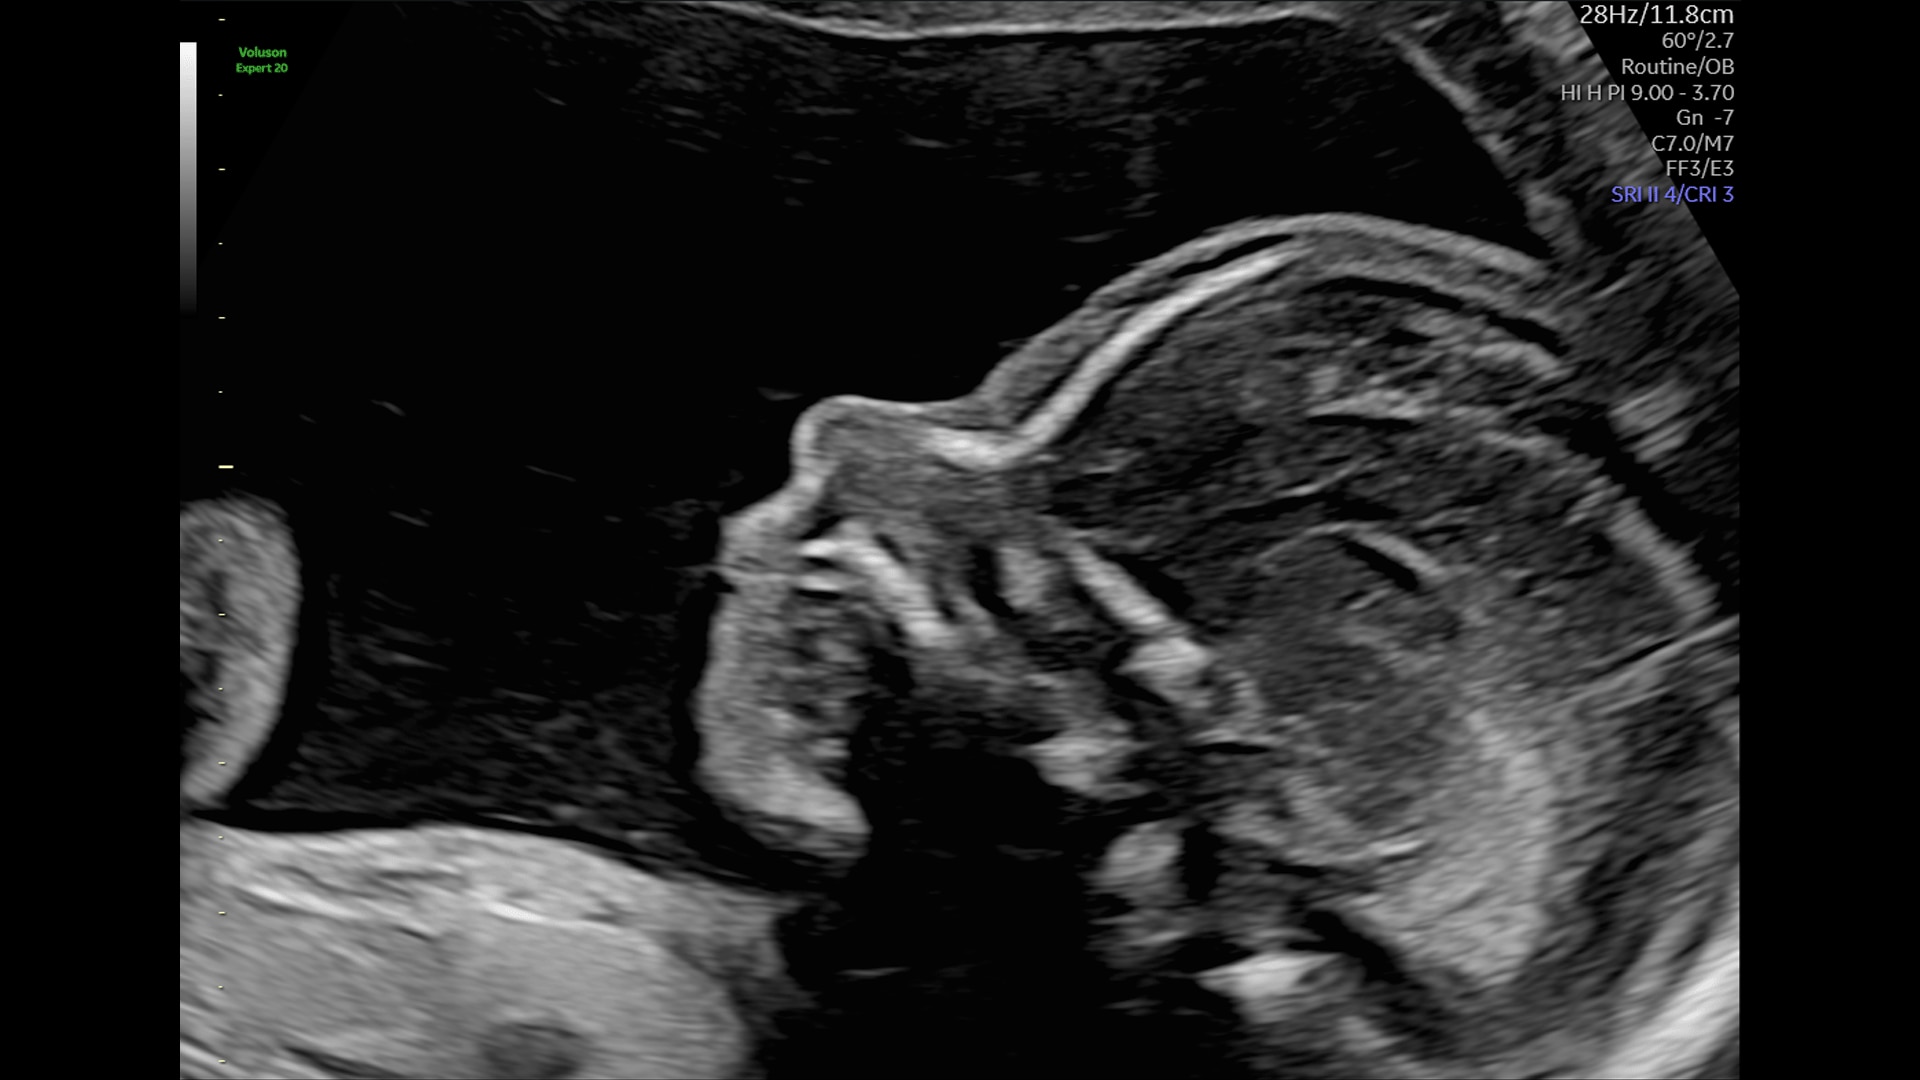

Amplify imaging performance and simplify scanning with our most advanced architecture

Extraordinary clarity and definition so you can focus on early detection and intervention.

Faster.Sharper. Clearer.

Faster.Sharper. Clearer.